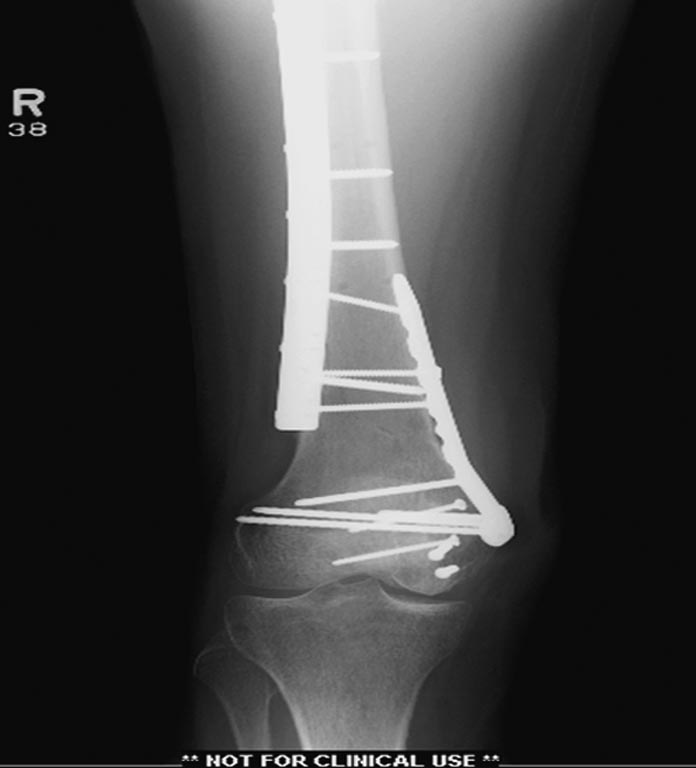

На 25 день с момента травмы операция на Jackson table с боковым обширным

доступом. Удаление стержней с местной обработкой. В тазобедренном

суставе удаление головки, на дне вертлужной впадины полная отслойка

хряща. Вертлужный компонент с одним винтом и короткая ножка -  Fitmore

Выписана. Нагрузку разрешили на левой стороне, а полная в 3 мес.  Здесь

снимки при амбулаторном наблюдении​: послеоперационно, 2 мес, 3 мес и 6

мес. Нагрузка полная, отсутствует хромота, и нет жалоб.